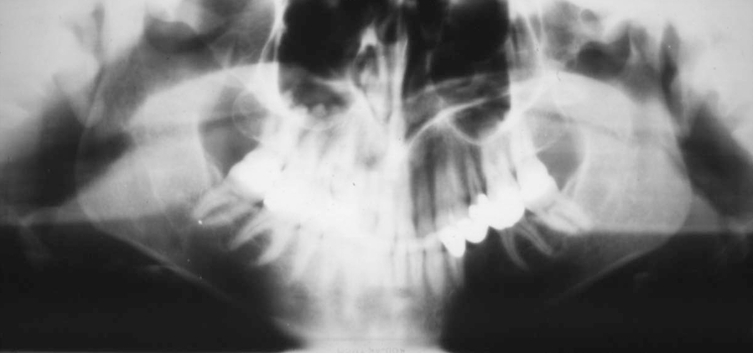

What is wrong with this image?

too far back

What happens if a panoramic is taken too far back?